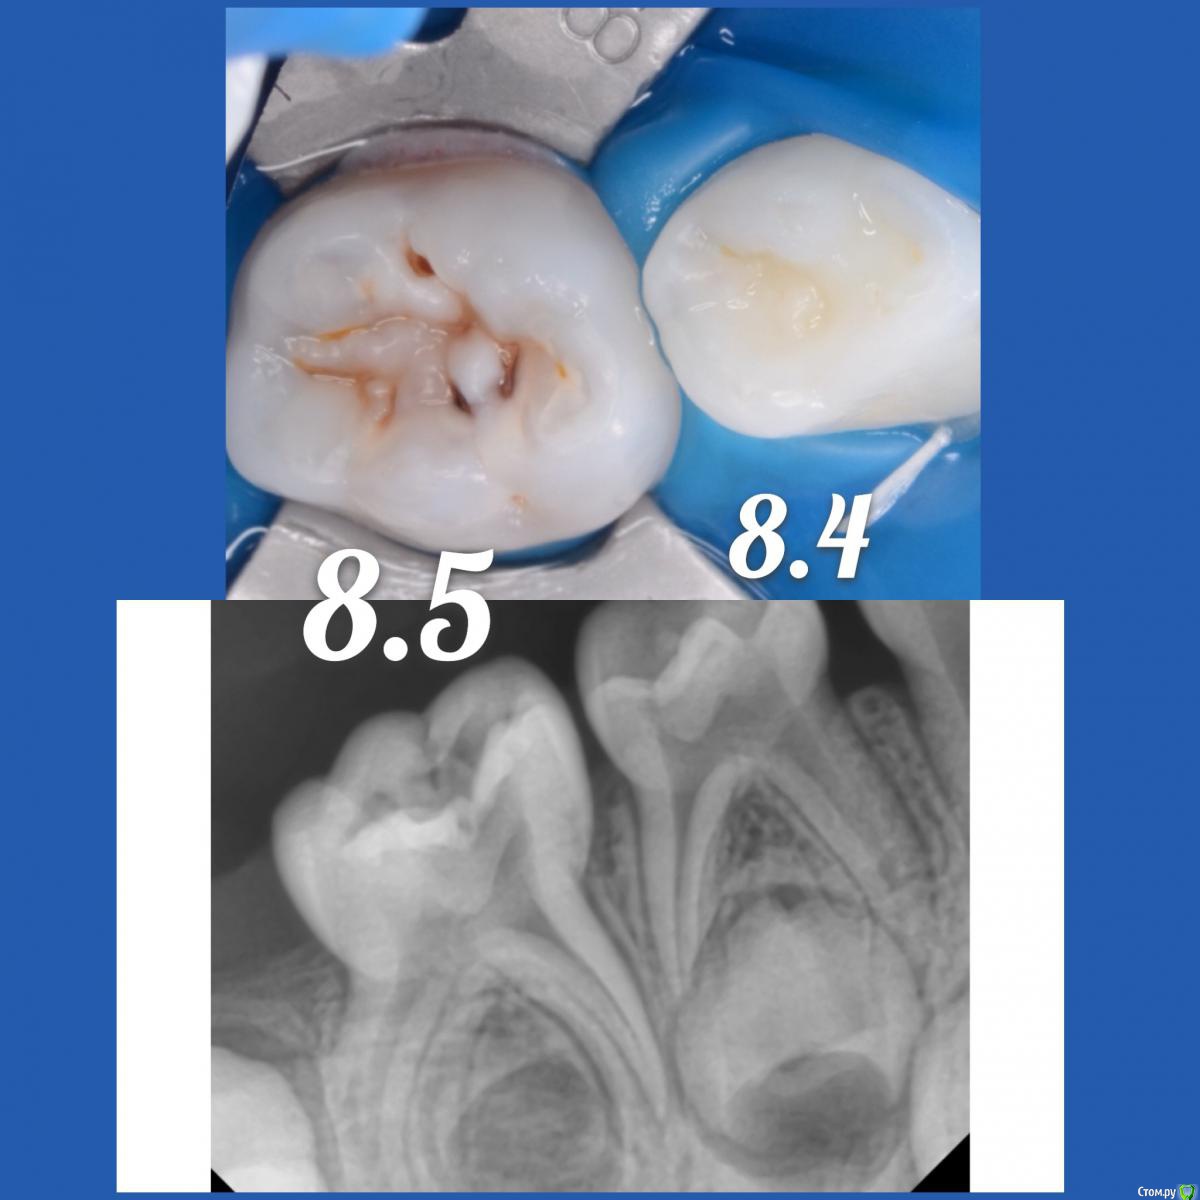

CRAZYDUCK Опубликовано 12 мая, 2018 Автор Поделиться Опубликовано 12 мая, 2018 Вероничке 4,5 годика . Очень веселая и контактная девчушка ( такой пирожочек сладенький , булочка 5 Ссылка на комментарий

CRAZYDUCK Опубликовано 12 мая, 2018 Автор Поделиться Опубликовано 12 мая, 2018 К предыдущему посту Но предстоящее лечение 8.5 все же сложное и это первый опыт . Как он пройдёт ? Не испугается ли онемения ? «Высидит» ли за один раз все ? Старшая сестричка Вероники очень боится лечить зубы ( с третьего визита позволила только почистить зубы ) . Был Негативный опыт , может повезёт и покажу и сестричку .Вероника молодцом ! Только устала , но выбор подарка после лечения ее взбодрил .Теперь по делу - экстирпация во временных зубах - это глубокая или очень глубокая ампутация. Наша задача удалить нерв , не выходя за апекс временного ( примерно на 2/3 длины канала ), моем гипохлоритом (!!!!) , сушим пылесосом ( можно одеть канюлю от метапекса - метапасты на насадку пылесоса и просушить в канале ( я ещё досушиваю бумажными пинами).Апекслокатор - не нужен ! Главное , чтобы из канала не кровило и было сухо . Инструментальная обработка Sx ( устьевик), потом ручными ( я чаще до 25.02 максимум прохожу ),пломбирую пастой Йодотин ( аналог метапекса), проверяем вне полости рта - идёт ли паста из канюли - вводим в устье , аккуратно выдавливаем - появилась паста в устье - начинаем вытягивать канюлю из канала ( одновременно выдавливая пасту ). Делаем то же самое с другими каналами и убираем излишки . Я перекрываю кальцимолом устья , под коронку восстанавливаю IRM. Фиксация Коронки без коффердама . Излишки цемента из межзубных промежутков убираю флоссом, посередине нитки делаем узелок , чтобы он помог вывести излишки . Фиксирую на айрекс цем .( с дёсны излишки цемента не убрала - устала Вероничка). Ссылка на комментарий